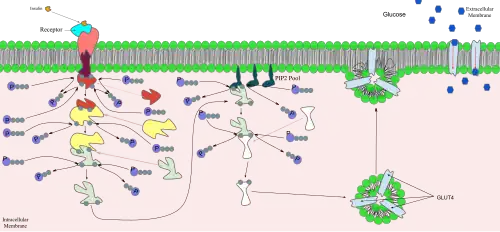

Insulin

Insulin is released from the pancreas and into the bloodstream in response to increased glucose concentration in the blood.[26] Insulin is stored in beta cells in the pancreas. When glucose in the blood binds to glucose receptors on the beta cell membrane, a signal cascade is initiated inside the cell that results in insulin stored in vesicles in these cells being released into the blood stream.[27] Increased insulin levels cause the uptake of glucose into the cells. GLUT4 is stored in the cell in transport vesicles, and is quickly incorporated into the plasma membrane of the cell when insulin binds to membrane receptors.[24]

Under conditions of low insulin, most GLUT4 is sequestered in intracellular vesicles in muscle and fat cells. As the vesicles fuse with the plasma membrane, GLUT4 transporters are inserted and become available for transporting glucose, and glucose absorption increases.[28] The genetically engineered muscle insulin receptor knock‐out (MIRKO) mouse was designed to be insensitive to glucose uptake caused by insulin, meaning that GLUT4 is absent. Mice with diabetes or fasting hyperglycemia, however, were found to be immune to the negative effects of the insensitivity.[29]

The mechanism for GLUT4 is an example of a cascade effect, where binding of a ligand to a membrane receptor amplifies the signal and causes a cellular response. In this case, insulin binds to the insulin receptor in its dimeric form and activates the receptor's tyrosine-kinase domain. The receptor then recruits Insulin Receptor Substrate, or IRS-1, which binds the enzyme PI-3 kinase. PI-3 kinase converts the membrane lipid PIP2 to PIP3. PIP3 is specifically recognized by PKB (protein kinase B) and by PDK1, which can phosphorylate and activate PKB. Once phosphorylated, PKB is in its active form and phosphorylates TBC1D4, which inhibits the GTPase-activating domain associated with TBC1D4, allowing for Rab protein to change from its GDP to GTP bound state. Inhibition of the GTPase-activating domain leaves proteins next in the cascade in their active form, and stimulates GLUT4 to be expressed on the plasma membrane.[30]

RAC1 is a GTPase also activated by insulin. Rac1 stimulates reorganization of the cortical Actin cytoskeleton[31] which allows for the GLUT4 vesicles to be inserted into the plasma membrane.[32][33] A RAC1 Knockout mouse has reduced glucose uptake in muscle tissue.[33]

Knockout mice that are heterozygous for GLUT4 develop insulin resistance in their muscles as well as diabetes.[34]